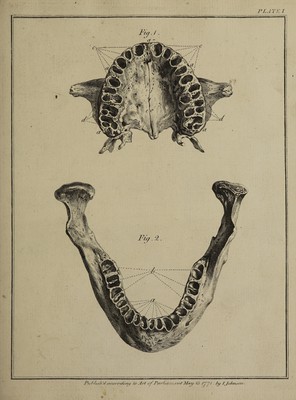

The natural history of the human teeth: explaining their structure, use, formation, growth, and diseases / By John Hunter.

- John Hunter

- 1778

Credit: The natural history of the human teeth: explaining their structure, use, formation, growth, and diseases / By John Hunter. Source: Wellcome Collection.